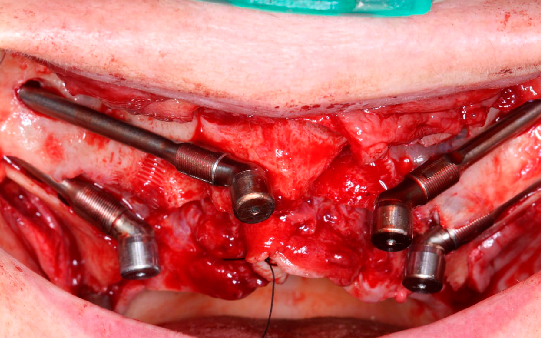

Protocolo em Resina Acrílica: boa estética, acessível, indicado para reabilitações com ótimo custo-benefício.